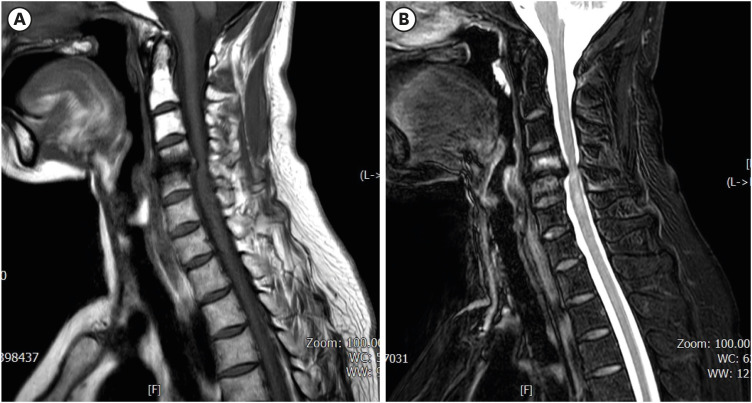

虽然颈椎椎间盘切除前路融合术(ACDF)是治疗颈椎病最常见的手术之一,但它也与各种术后并发症有关。食管穿孔是一种罕见但非常严重的 ACDF 术后并发症,而螺钉从口腔挤出的病例则更为罕见。在此,我们介绍了一名 61 岁女性的病例,她在接受 ACDF 手术 6 个月后因螺钉从口腔挤出而到我们的急诊中心就诊。虽然影像诊断没有证实食管穿孔,但螺钉经口挤出是并发症的明显证据。据我们所知,这是第一例未确诊食管损伤的口腔螺钉挤出病例。该病例表明,螺钉移位和食管穿孔的发生取决于患者的基础情况,如果症状轻微,仅靠保守治疗可能就足以治疗穿孔。

Although anterior cervical discectomy and fusion (ACDF) is one of the most common surgical procedures performed for the treatment of cervical disease, it is associated with a variety of postoperative complications. Esophageal perforation is a rare but very serious post-ACDF complication, and cases in which screws extrude through the mouth are even rarer. Herein, we present the case of a 61-year-old woman who visited our emergency center with oral extrusion of a screw 6 months after undergoing ACDF. Although diagnostic imaging did not confirm esophageal perforation, the oral extrusion of the screw was clear evidence of the complication. To the best of our knowledge, this is the first reported case of oral screw extrusion without confirmed esophageal injury. This case suggests that screw migration and esophageal perforation can occur depending on the patient's underlying condition, and if the symptoms are mild, conservative treatment alone may be sufficient to treat the perforation.